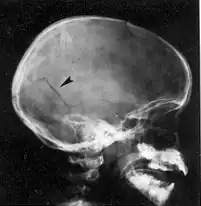

Fracturas de cráneo

A pesar de que el cráneo es una estructura ósea sólida con una gran resistencia es común que resulte fracturado si el impacto ejerce una presión excesiva sobre él,[3] ya sea por una fuerza elevada o por un área pequeña de contacto. Las fracturas de cráneo resultan de un impacto en la cabeza que por lo general es lo suficientemente grave como para provocar al menos una breve pérdida de conciencia.[15] Las fracturas de cráneo lineales son grietas sin desplazamiento de estructuras óseas a través del cráneo. Si el trauma es muy intenso puede causar un hueco o diastasis entre los bordes de la fractura. Una fractura en la cual el hueso se desplaza al interior de la cavidad craneal una distancia mayor que el grosor del hueso se llama fractura craneal desplazada.[14] La fractura craneal desplazada con fragmentos de cráneo empujados hacia la bóveda craneal es más común en un traumatismo craneoencefálico causado por un objeto con una superficie de contacto pequeña como un martillo. El tipo más común de fractura de cráneo es una fractura lineal sobre las convexidades laterales del cráneo.[15][13]

Un trauma ocular contuso en la frente o el occipucio puede causar fracturas en la base del cráneo. Tales fracturas de base de cráneo son más comunes en la base craneal anterior y a menudo afectan a la lámina cribosa. Esto altera los nervios olfatorios y puede causar la pérdida del sentido del olfato. Las fracturas de base craneal posterior pueden extenderse a través de la porción petrosa del hueso temporal y el conducto auditivo interno lo que daña el nervios acústicos o el nervio facial conduciendo a la pérdida de audición sensorio-neural o parálisis facial.[15]

El significado clínico de las fracturas de cráneo está en relación con el daño asociado en el tejido subyacente, los vasos o nervios craneales más que a la propia fractura. Las fracturas de cráneo lineales que involucran la porción escamosa del hueso temporal pueden romper la arteria meníngea media desencadenando un hematoma epidural. Las fracturas con hundimiento del cráneo se asocian con contusiones del tejido cerebral subyacente. Si el cuero cabelludo que recubre el fragmento de cráneo con hundimiento está lacerado, el fragmento de hueso deprimido es propenso a ser contaminado con bacterias de la piel lo que puede conducir a la formación de abscesos cerebrales o encefalitis.[30] Las fracturas de la base del cráneo a menudo están asociados con la ruptura de la duramadre subyacente lo que resulta en fístulas con la fosa nasal, senos paranasales u oído. Esto que constituye una vía más de entrada de microorganismos y fugas de líquido cefalorraquídeo por la nariz o el oído.[15] Las fístulas son un conducto para la contaminación bacteriana del espacio intracraneal de la nariz, senos paranasales, o en el conducto auditivo externo.[30]

- Radiografía simple de cráneo: que es de utilidad para localizar fracturas en el cráneo que pudiesen generar un hematoma epidural, o localizar un cuerpo extraño dentro del cráneo. Suele indicarse cuando existe contusión o laceración de la piel cabelluda o herida con profundidad hasta el hueso. Tiene la ventaja de ser barata, inocua, sencilla y relativamente rápida.